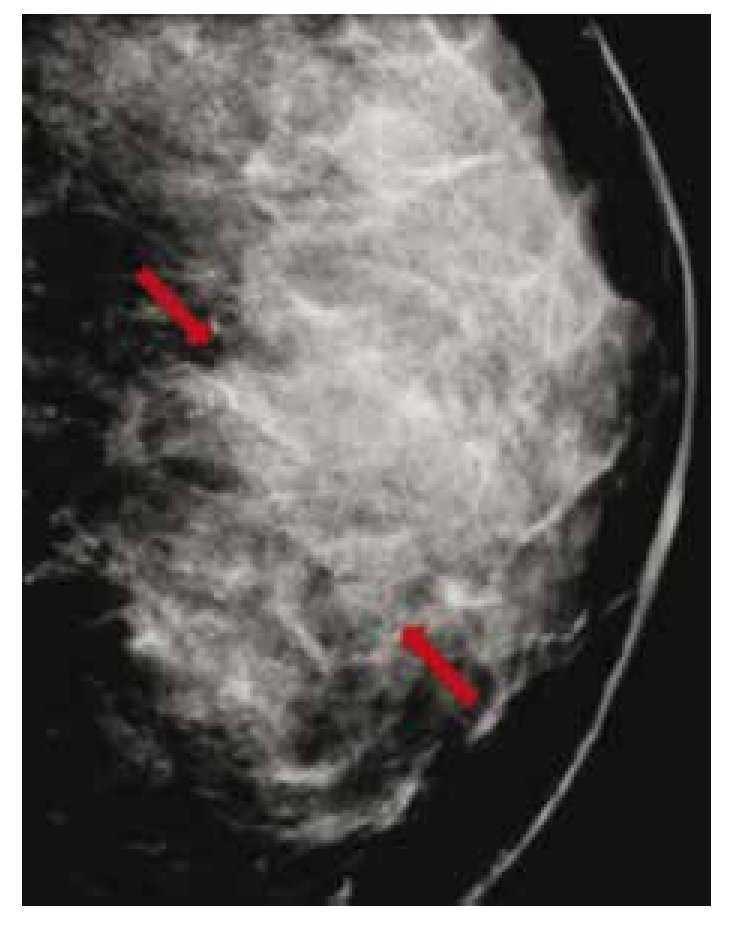

Figura 3 Asintomática, paciente de 41 años con grupos de microcalcificaciones polimorfas izquierdas de distribución lineal (flechas), BIRADS 4C: hiperplasia ductal con atipia.